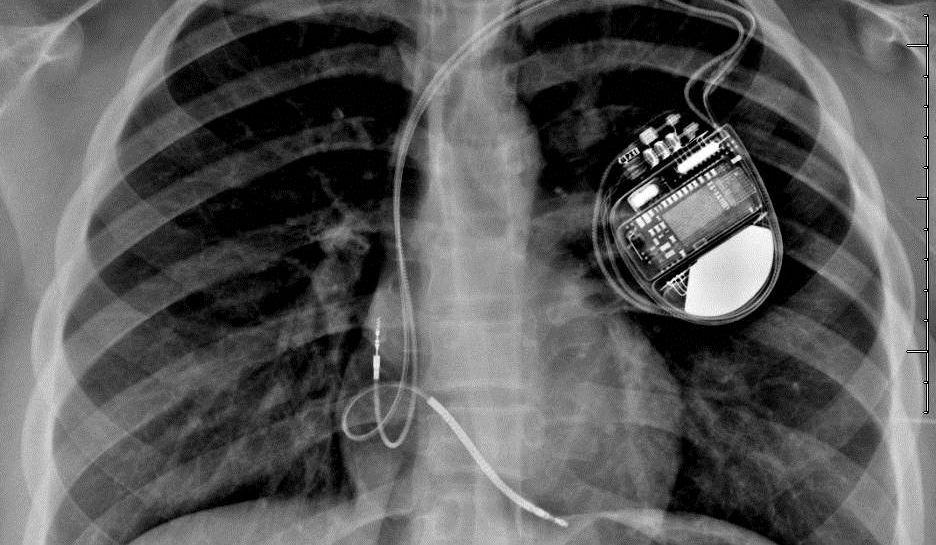

Hackerii îți pot ataca inima! Sute de mii de stimulatoare cardiace sunt vulnerabile la atacuri cibernetice!